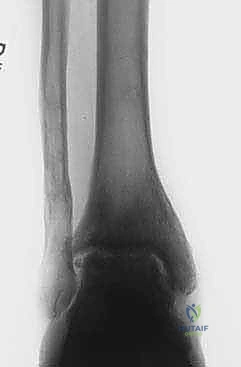

- الأشعة السينية (X-rays) مع الوقوف: لتقييم المسافة المتبقية من المفصل وتحديد درجة الخشونة ومحور الساق.

- الأشعة المقطعية (CT Scan): للحصول على صورة ثلاثية الأبعاد للعظام، واكتشاف أي تكيسات عظمية (Bone cysts) أو نتوءات عظمية (Osteophytes).

على عكس الركبة والورك حيث تكون الخشونة غالباً بسبب التقدم في العمر، فإن أكثر من 70% من حالات خشونة الكاحل تحدث نتيجة إصابات سابقة (Post-traumatic Osteoarthritis).

كسور الكاحل، الالتواءات المتكررة، أو تمزق الأربطة غير المعالج يؤدي إلى اختلال ميكانيكية المفصل. هذا الاختلال يسبب تركز الضغط على مناطق معينة من الغضروف، مما يؤدي إلى تآكله السريع، وموت الخلايا الغضروفية، وانكشاف العظم الذي تحته، وهو ما يسبب الألم المبرح.

- زيادة مساحة المفصل: تظهر الأشعة السينية بوضوح اتساع المسافة بين عظام الكاحل، وهو دليل قاطع على تجدد النسيج الغضروفي.